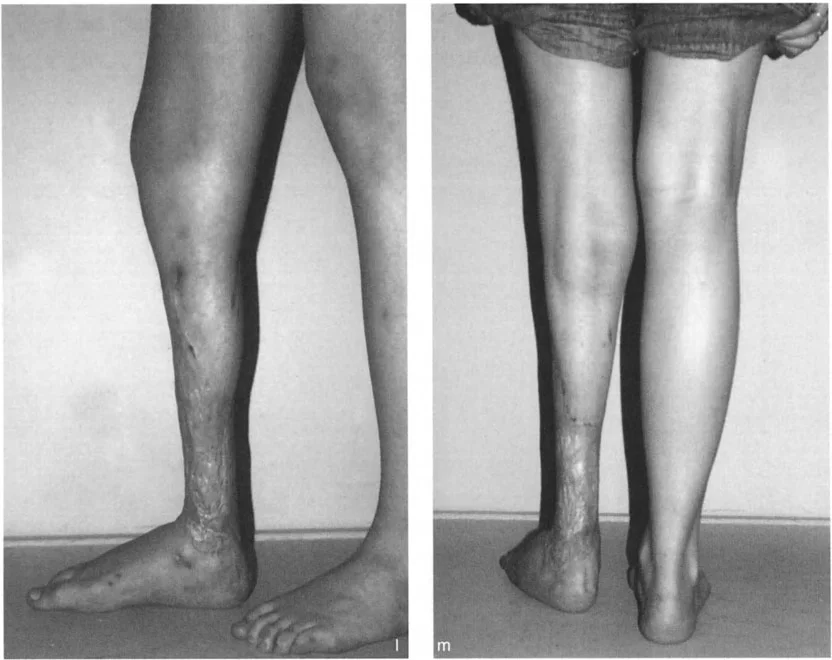

أعراض تشوهات الكاحل والقدم

تتنوع أعراض تشوهات الكاحل والقدم بشكل كبير اعتمادًا على نوع التشوه وشدته، ولكنها تشترك في تأثيرها السلبي على جودة حياة المريض. من الضروري الانتباه لهذه الأعراض والبحث عن استشارة طبية مبكرة لتجنب تفاقم الحالة.

الأعراض الشائعة لتقوس الكاحل

- صعوبة في المشي (العرج): يعتبر هذا من أبرز الأعراض، حيث يجد المريض صعوبة في وضع الكعب على الأرض بشكل طبيعي، مما يجعله يمشي على مقدمة القدم أو جانبها.

- تشوه واضح في شكل القدم أو الكاحل: قد يلاحظ المريض أو المحيطون به تغيرًا في شكل القدم، مثل ارتفاع القوس بشكل مفرط في حالة القدم الجوفاء، أو انحراف الكاحل.

تؤثر هذه الأعراض بشكل مباشر على جودة حياة المريض، وتحد من قدرته على ممارسة الأنشطة اليومية والرياضية. لذلك، فإن التشخيص المبكر والعلاج الفعال ضروريان لتجنب المضاعفات طويلة الأمد واستعادة الوظيفة الطبيعية للقدم والكاحل. يعتمد الأستاذ الدكتور محمد هطيف على تقييم شامل للأعراض والتاريخ المرضي لتحديد أفضل نهج تشخيصي وعلاجي لكل مريض.